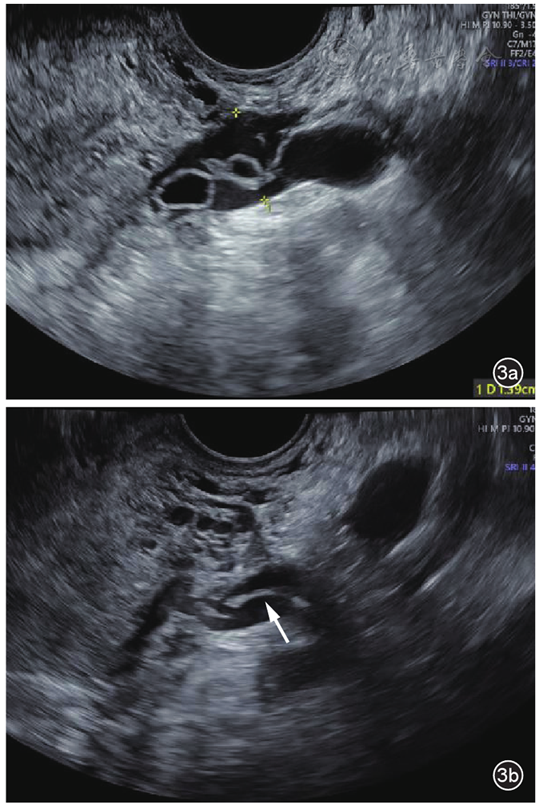

综合临床表现、实验室检查及影像学特征,临床诊断为高危型妊娠滋养细胞肿瘤Ⅱ期,预后评分7分。患者接受了更生霉素联合拓益(PD-1抑制剂)化疗,共8个疗程。化疗期间,患者血β-hCG水平逐渐降至正常。化疗7个疗程后复查经阴道超声显示左侧宫旁静脉扩张较前明显减轻,较宽处约0.8 cm,其内见少许条索样中等回声,宽约0.2 cm,未见明确囊泡状无回声,余盆腔静脉及髂静脉内未见异常回声(图3);盆腔增强MRI显示左侧附件区多发异常信号及血管流空影较前减小,子宫肌层信号不均较前稍减轻,提示治疗效果显著。本研究经北京协和医院伦理委员会审批同意(批件号:I-24PJ2530)。

图3 盆腔静脉侵袭性葡萄胎患者化疗前、后左侧宫旁静脉病灶变化超声对比图像。图a为化疗前宫旁扩张静脉内可见多个囊泡状无回声;图b为化疗后左侧宫旁静脉扩张较前减轻,管腔内囊泡状无回声消失,仅见少许条索状中等回声(箭头所示)